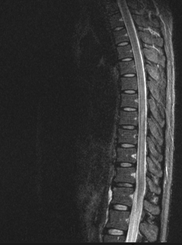

A 26-year-old man was admitted in our Rehabilitation Unit in May 2022 after being diagnosed with TBM. The patient presented to the emergency department with a 2-week history of fever, disorientation, decreased lower limbs strength and urinary incontinence. He had a recent history of contact with tuberculosis (TB), with a positive interferon gamma release assay test. Brain magnetic resonance imaging (MRI) with gadolinium contrast revealed hydrocephalus and diffuse leptomeningeal enhancement with basal cistern involvement (Figure 1). Acute ischemic brain lesions with hemorrhagic transformation in the right globus pallidus and anterior limb of internal capsule consistent with infarctions due to infectious arteritis, were also noted (Figures 2 & 3). Spine MRI with gadolinium contrast revealed diffuse cervical, thoracic, lumbar and sacral enhancement of meninges overlying the spinal cord and cauda equina nerve roots (Figure 4). These images were suggestive of TB infection. Blood cultures, serologies and cerebrospinal fluid (CSF) culture were negative for TB bacilli and he had no relevant medical history, including risk factors for being immunocompromised. Nevertheless, presumptive diagnosis of TBM was made in the setting of relevant clinical and epidemiologic factors in combination with typical CSF and MRI findings.

Figure 4 Spine MRI with gadolinium contrast, sagittal view - diffuse cervical, thoracic, lumbar and sacral enhancement of meninges overlying spinal cord.